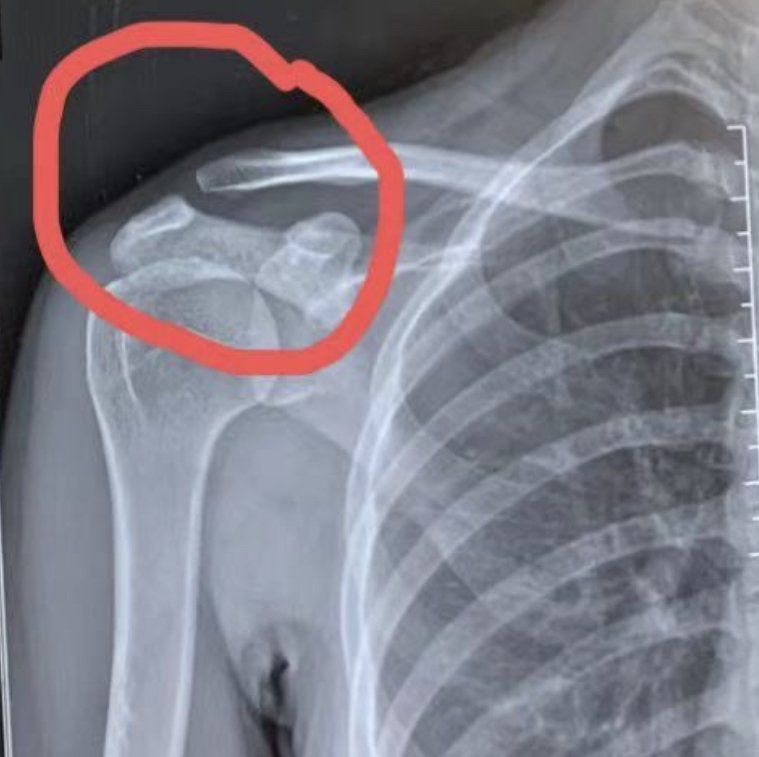

운동 후 다쳤는데 괜찮을까요?

사실 저는 아니고 제 지인이 간단한 홈트 후 어깨뼈 통증이 있어서 병원에 갔는데 통증이 심해지면 수술해야한다네요

혹시 회전근개나 그런곳 다친건 아닌지 걱정도 되네요ㅠ

• 1번 째 사진